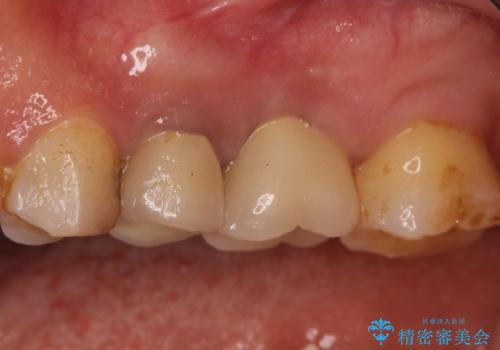

- 以前から奥歯に違和感があることを主訴に来院されました。歯肉にサイナストラクトを認めたため、再根管治療を行った後オールセラミッククラウンにて修復治療を行いました。根管治療は林先生に依頼しております。

- 13万円(根管治療別途)費用は治療当時の料金となります